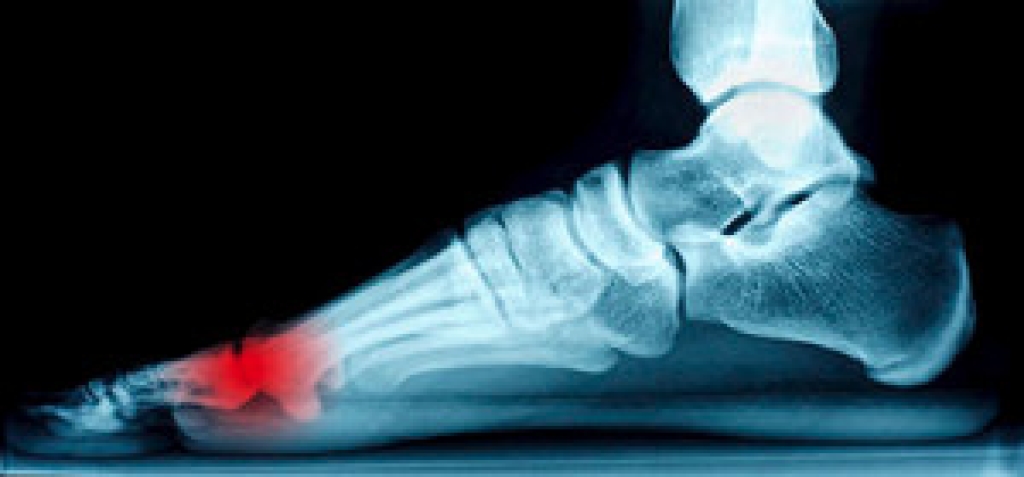

The sesamoid bones are located under the joints of the big toe. They are small, about the size of a pea, and are found within the soft tissues. Their function is to absorb pressure while standing and walking, in addition to easing friction as the big toe is moved. The medical condition that is known as sesamoiditis can occur when the sesamoid bones become inflamed. This can happen from practicing repetitive movements such as running and dancing. Additionally, sesamoiditis may occur due to existing conditions such as arthritis, stress fractures, or high arches. Mild relief may be found when protective pads are worn, which may help to cushion the sesamoid bones. If you have developed sesamoiditis, please consult with a podiatrist who can properly treat this condition.

Sesamoiditis is a condition of the foot that affects the ball of the foot. It is more common in younger people than it is in older people. It can also occur with people who have begun a new exercise program, since their bodies are adjusting to the new physical regimen. Pain may also be caused by the inflammation of tendons surrounding the bones. It is important to seek treatment in its early stages because if you ignore the pain, this condition can lead to more serious problems such as severe irritation and bone fractures.